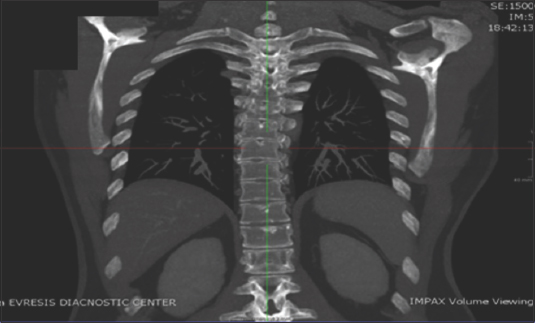

Further investigations, including computed tomography (CT) imaging of the thoracic bony cage, demonstrated multiple foci of bony sclerosis (Fig. 3). On provisional histological examination of the bone marrow, multifocal infiltrates of atypical mast cells were observed, confirming the diagnosis of SM. Considering all aforementioned findings, the consultant hemato-oncologist confirmed the diagnosis of an indolent form of SM. As a result, there are currently no indications for this patient to start any type of treatment. The hemato-oncologist recommended that the patient be followed up with blood tests at regular intervals of 3 months. After a few months the patient complained of abdominal distention; a gastroscopy was performed but revealed no pathological findings.

Figure 3 Computed tomography scan. Imaging of the thoracic bony cage demonstrates multiple foci of bony sclerosis

Last but not least, the patient’s CT scan revealed multiple bony sclerosis in the thorax. Although not specific, along with the rest of the findings, this increases suspicion of the diagnosis. Those findings could be attributed to mastocytosis, either because of new bone formation or by the presence of protease, a mast cell mediator, which can lead to bony lesions [7].